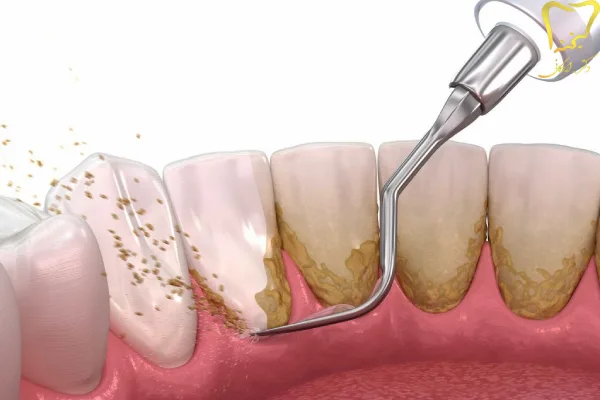

این میکروب ها براحتی و کم کم بر روی دندان ها می چسبند. در ابتدا این لایه رسوب نرم و قابل شستشو و از بین بردن می باشند. اما به مرور زمان حتی بعد از گذشت یک یا دو روز این لایه ها اگر پاکسازی نگردند تبدیل به یک رسوب بسیار سخت می شوند. این رسوب ها سخت شده اند و دیگر با مسواک پاک نمی شوند و نیازمند جرمگیری دندان دارند.

جرم گیری و بروساژ کامل دندان می تواند جرم موجود در بالا و زیر لثه را از بین ببرد. گاهی رسوب های زیر لثه، رنگی سیاه و یا مایل به قهوه ای دارند. این رسوب ها در تحلیل ریشه دندان و لثه بسیار اثرگذار می باشند.

پس از حذف جرم ها و رسوب های سفت و سخت مرحله بروساژ دندان انجام می شود. در واقع با اجرای این کار فضا برای باکتری ها کم شده و امکان رشد مجدد کاهش می یابد.

استفاده از ابزارهای جرم گیری:

دندانپزشک از ابزارهایی مثل ابزارهای دستی، اولتراسونیک یا لیزر برای از بین بردن جرم و پلاک دندانی کمک می گیرد.

- هدف: هدف از جرم گیری، برداشتن پلاک و جرم از سطح دندان ها و لثه ها است. هدف از بروساژ صیقل دادن سطح دندان ها است.

- ابزار: برای جرم گیری از ابزارهای دستی یا دستگاه های التراسونیک کمک گرفته می شود. برای بروساژ از برس و خمیر دندان استفاده می شود.